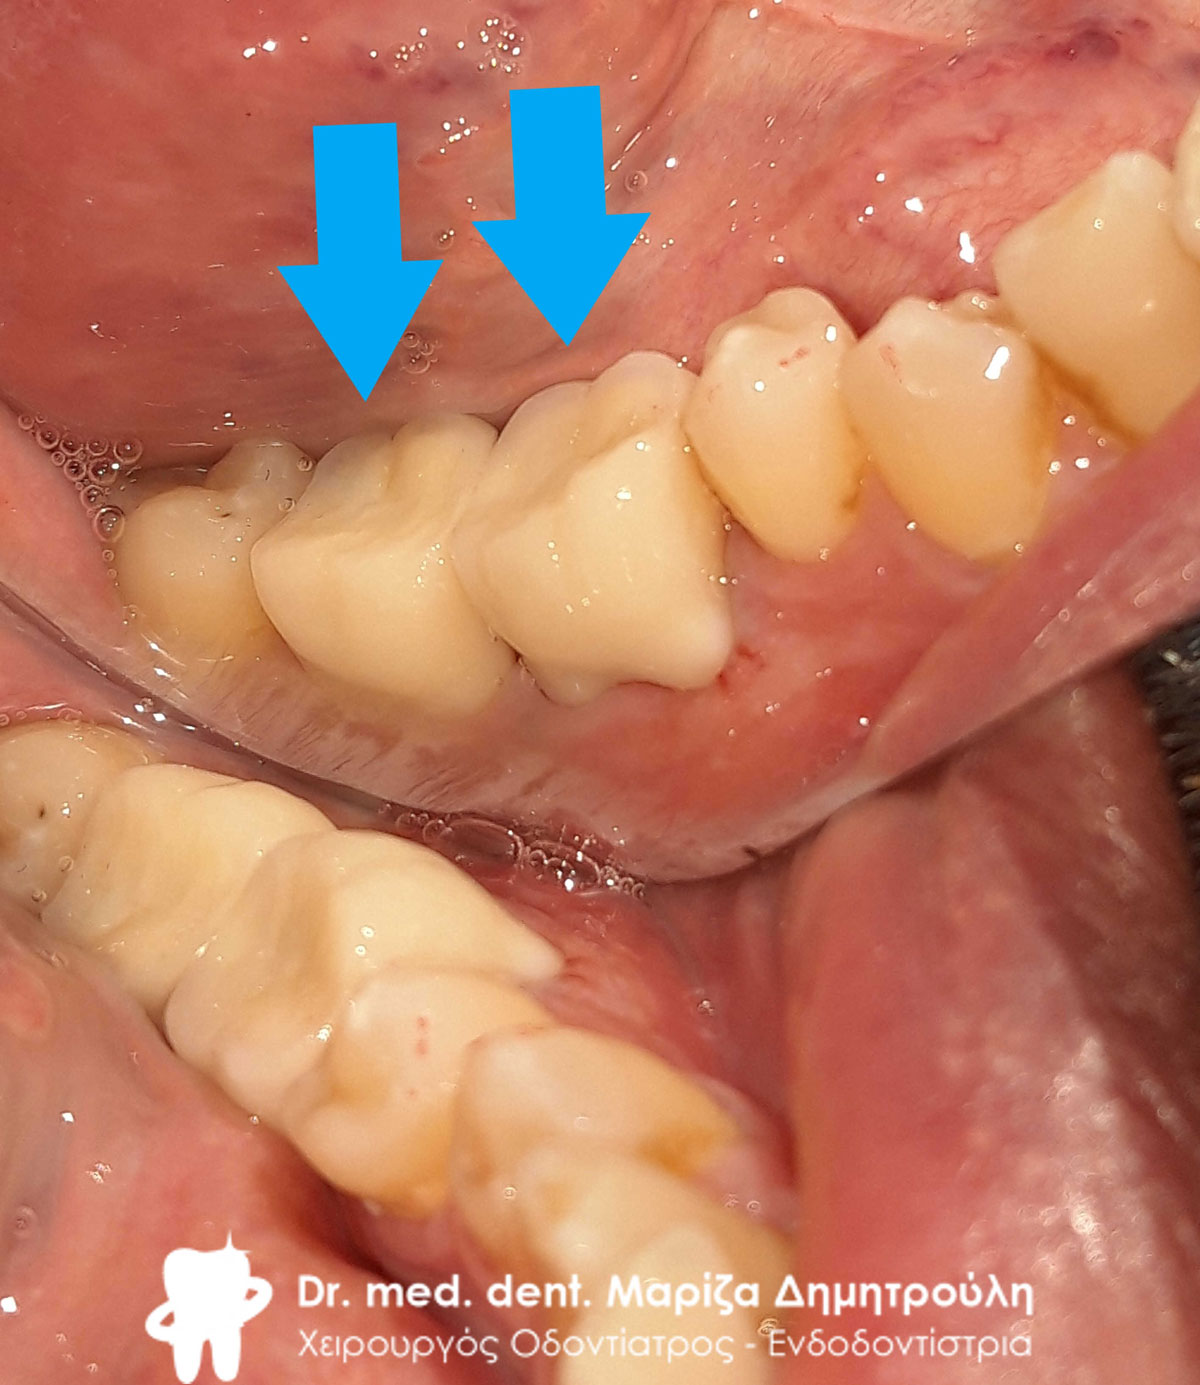

Περιστατικό – Ολοκεραμικό επένθετο ζιρκονίου στον άνω αριστερό γομφίο

Στη συγκεκριμένη ασθενή πραγματοποιήθηκε απονεύρωση δοντιού. Το οδοντικό έλλειμμα ήταν μεγάλο, οπότε το δόντι μετά την απονεύρωση έπρεπε να αποκατασταθεί είτε με θήκη δοντιού είτε με ολοκεραμικό ένθετο. Τελικά αποφασίστηκε η αποκατάσταση με ένθετο δοντιού, γιατί χρειάστηκε να θυσιαστεί λιγότερη οδοντική ουσία. Η ασθενής είναι ευχαριστημένη τόσο με τη λειτουργικότητα όσο και με το αισθητικό αποτέλεσμα.

Αρχική κλινική εικόνα του μεγάλου οδοντικού ελλείμματος

Τελική κλινική εικόνα του ολοκεραμικού επένθετου στο γομφίο